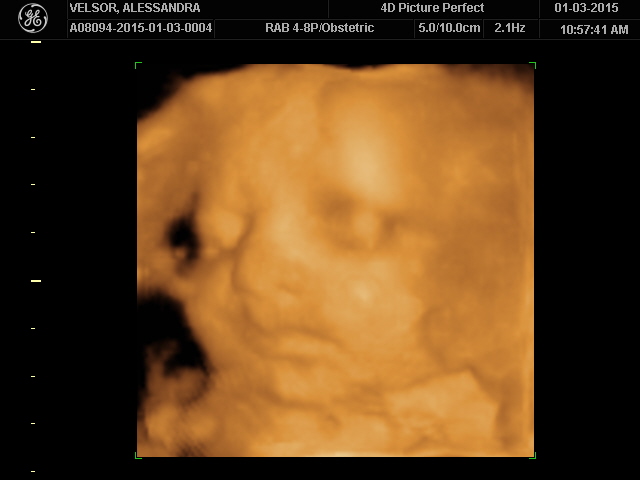

But I finally saw him.

I really really saw him.

I couldn’t believe we were carrying our future.

Our next generation.

Our Promise.